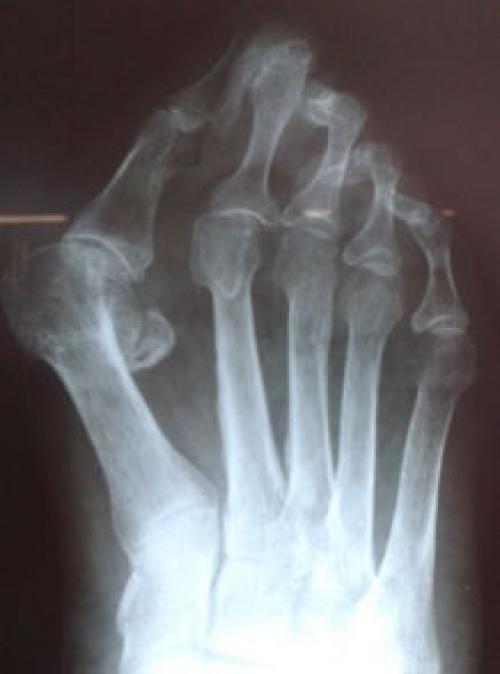

Для рентгенологической диагностики используются главным образом снимки в прямой проекции с нагрузкой. При этом оценивается 4-5 межплюсневый угол, 5 плюсне-фаланговый угол, ширина головки 5 плюсневой кости, угол наружного отклонения 5 плюсневой кости.

Выпирает косточка на ноге возле мизинца. Патогенез вальгусной деформации стопы

В результате ослабления мышечно-связочного аппарата стопы и неправильной нагрузки происходит изменение точек опоры и уплощение поперечного и продольного сводов.

Нагрузка и опора переходит на все плюснефаланговые суставы, что приводит к веерообразному расхождению костей переднего отдела стопы.Происходит дисбаланс мышечной силы, которая держит первый палец ровно, в результате он отклоняется, и искривление прогрессирует.

Значимым смещением костей первого пальца кнаружи считается смещение более чем на 10 градусов. Параллельно изменения происходят в капсульно-связочном аппарате — растяжение наружных отделов, смещение сесамовидного гамака.

Варусная деформация 5-го пальца (деформация тейлора) – патологическое состояние, при котором V палец отклоняется внутрь, а плюсневая кость кнаружи, появляется шишка у основания V пальца.

Диагностика

- клинический осмотр пациента ортопедом (клиническая картина);

- жалобы пациента, анамнез заболевания;

- рентгенография стопы и плантография.